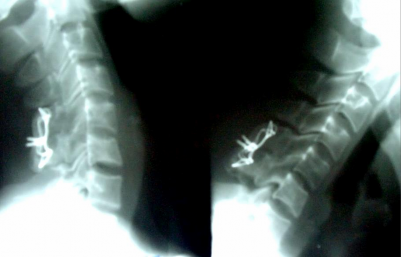

TRƯỚC MỔ (9 – 4 – 2008) HÌNH NGHIÊNG

(Trật 2 MK C4-C5/ CSC thoái hóa)

HÌNH CHÉO ¾

(Trật 2 mỏm khớp C4-C5)

SAU M

Trật mỏm khớp bên P – trật mỏm khớp bên T.

SAU MỔ (27 - 5 – 2008)

(Nắn vào tốt, cố định tốt)

HÌNH THẲNG HÌNH NGHIÊNG